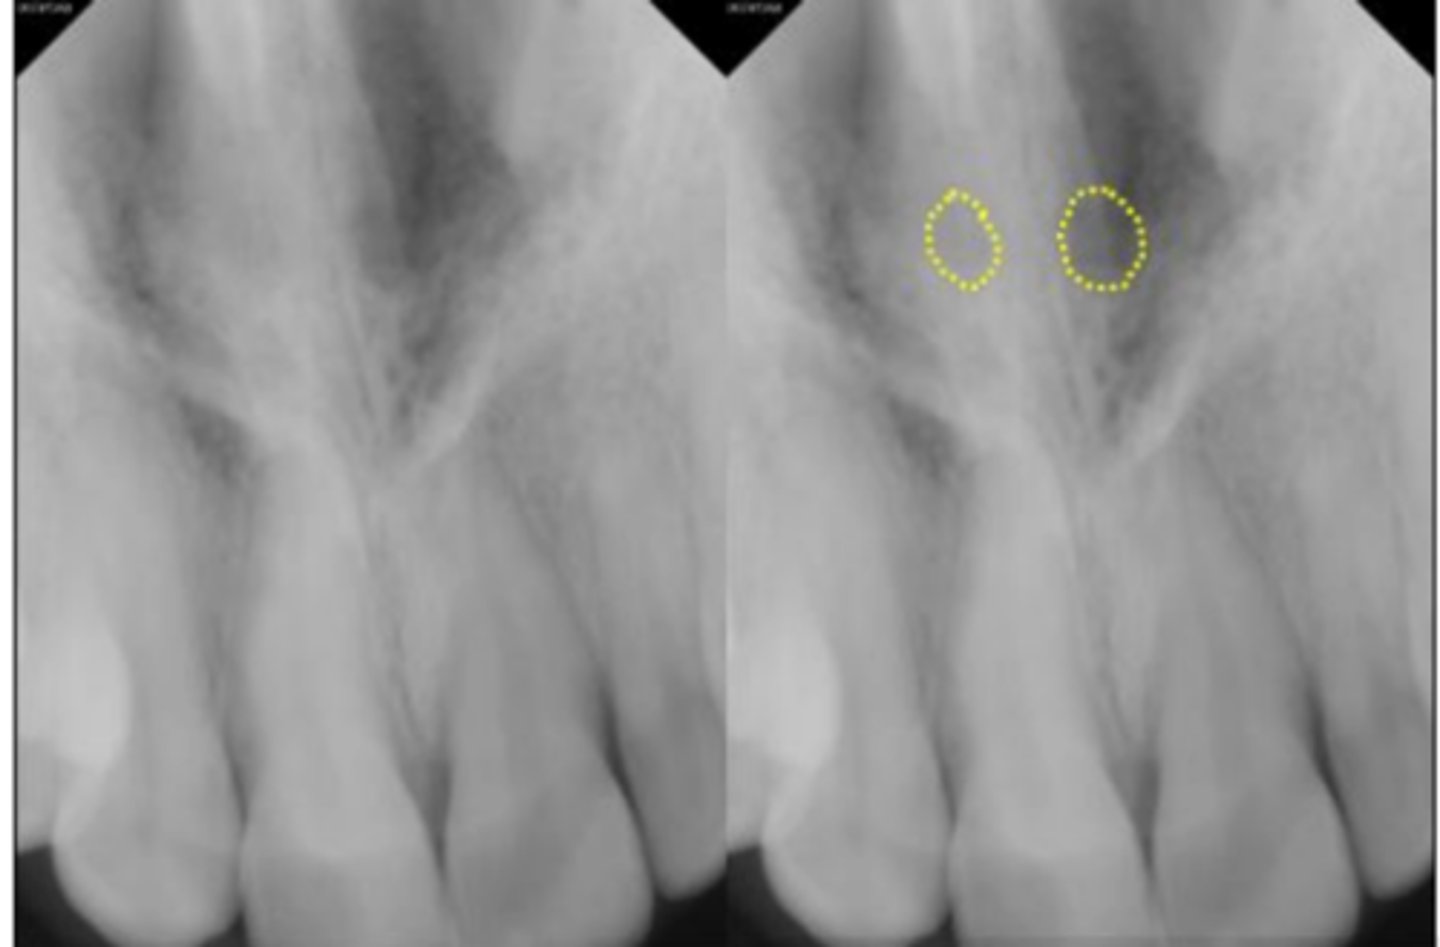

51

New cards

Superior foramina of the nasopalatine duct

Name the two round radiolucencies indicated.

<p>Name the two round radiolucencies indicated.</p>